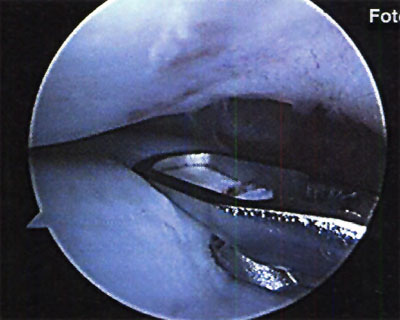

En cuanto a la localización de la lesión, 1 (2,4%) paciente presentó una localización anterior, 12 (29,3%) anterolateral, 23 (56,1%) posteromedial y 5 (12,2%) central. No se pudo explicar claramente esta distribución. (fotos 1 y 2) En cuanto a los casos presentados, los estudios radiográficos pusieron en evidencia la lesión en solo 36,6% de los pacientes, en 26 (63,4%) las radiografías fueron negativas (GI) mientras que de los casos positivos, 6 (14,6%) presentaron una lesión GIl, 6 (14,6 %) presentaron una lesión GIl y 3 pacientes (7,3%) una lesión G IV. (fotos 3 y 4)

Foto 1: lesión anterolateral

Foto 2: lesión posteromedial.

En relación al tratamiento quirúrgico, se realizó debridamiento de la lesión en 6 (26,1%) pacientes, debridamiento y perforaciones en 12 pacientes (52,2%) y en 5 pacientes se efectuó injerto osteocondral (21,7%). (fotos 11 y 12 )

Foto 11: Debridamiento y Perforaciones

Foto 12: cuerpo libre intraarticular